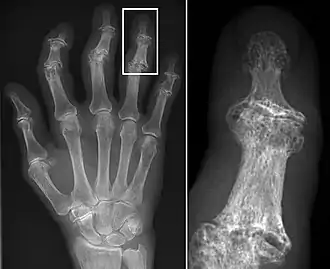

Trauma

Traumatic skeletal lesions are divided into fractures, dislocations, and surgical procedures. Trauma research within the context of archaeological human groups can provide important insights into aspects of past warfare, intra-group violence, and occupational accident rates.[23][24] The study of trauma can also help explore aspects of ancient care and social support as attested through the knowledge of ancient medicine.[25]

Sherry Fox from the Arizona State University, and her colleagues, explored traumatic patterns from different Early Christian church/basilica sites in Cyprus: Agios Georgios Hill, Nicosia, Kalavasos-Kopetra, Alassa-Ayia Mavri, and Maroni-Petrera. The Hill of Agios Georgios is situated inland adjacent to the Pediaios River outside the Venetian walled city of Nicosia, while the rest of the sites are located near the south coast. The aim of the study was to identify trauma patterns between the smaller, coastal sites and the larger, inland site. Trauma patterns, attributed to demographic differences, were evident between the inland and coastal sites, with a higher prevalence attested at the inland site of the Hill of Agios Georgios. A second difference was that males at the Hill of Agios Georgios had a higher propensity for traumatic lesions in the upper body and hand extremities, and this has been suggested to be caused by reasons beyond demographic parameters. The authors suggest that additional factors such as cultural, behavioral, and/or occupational differences, may account for the differences observed between the inland and coastal sites.[26]